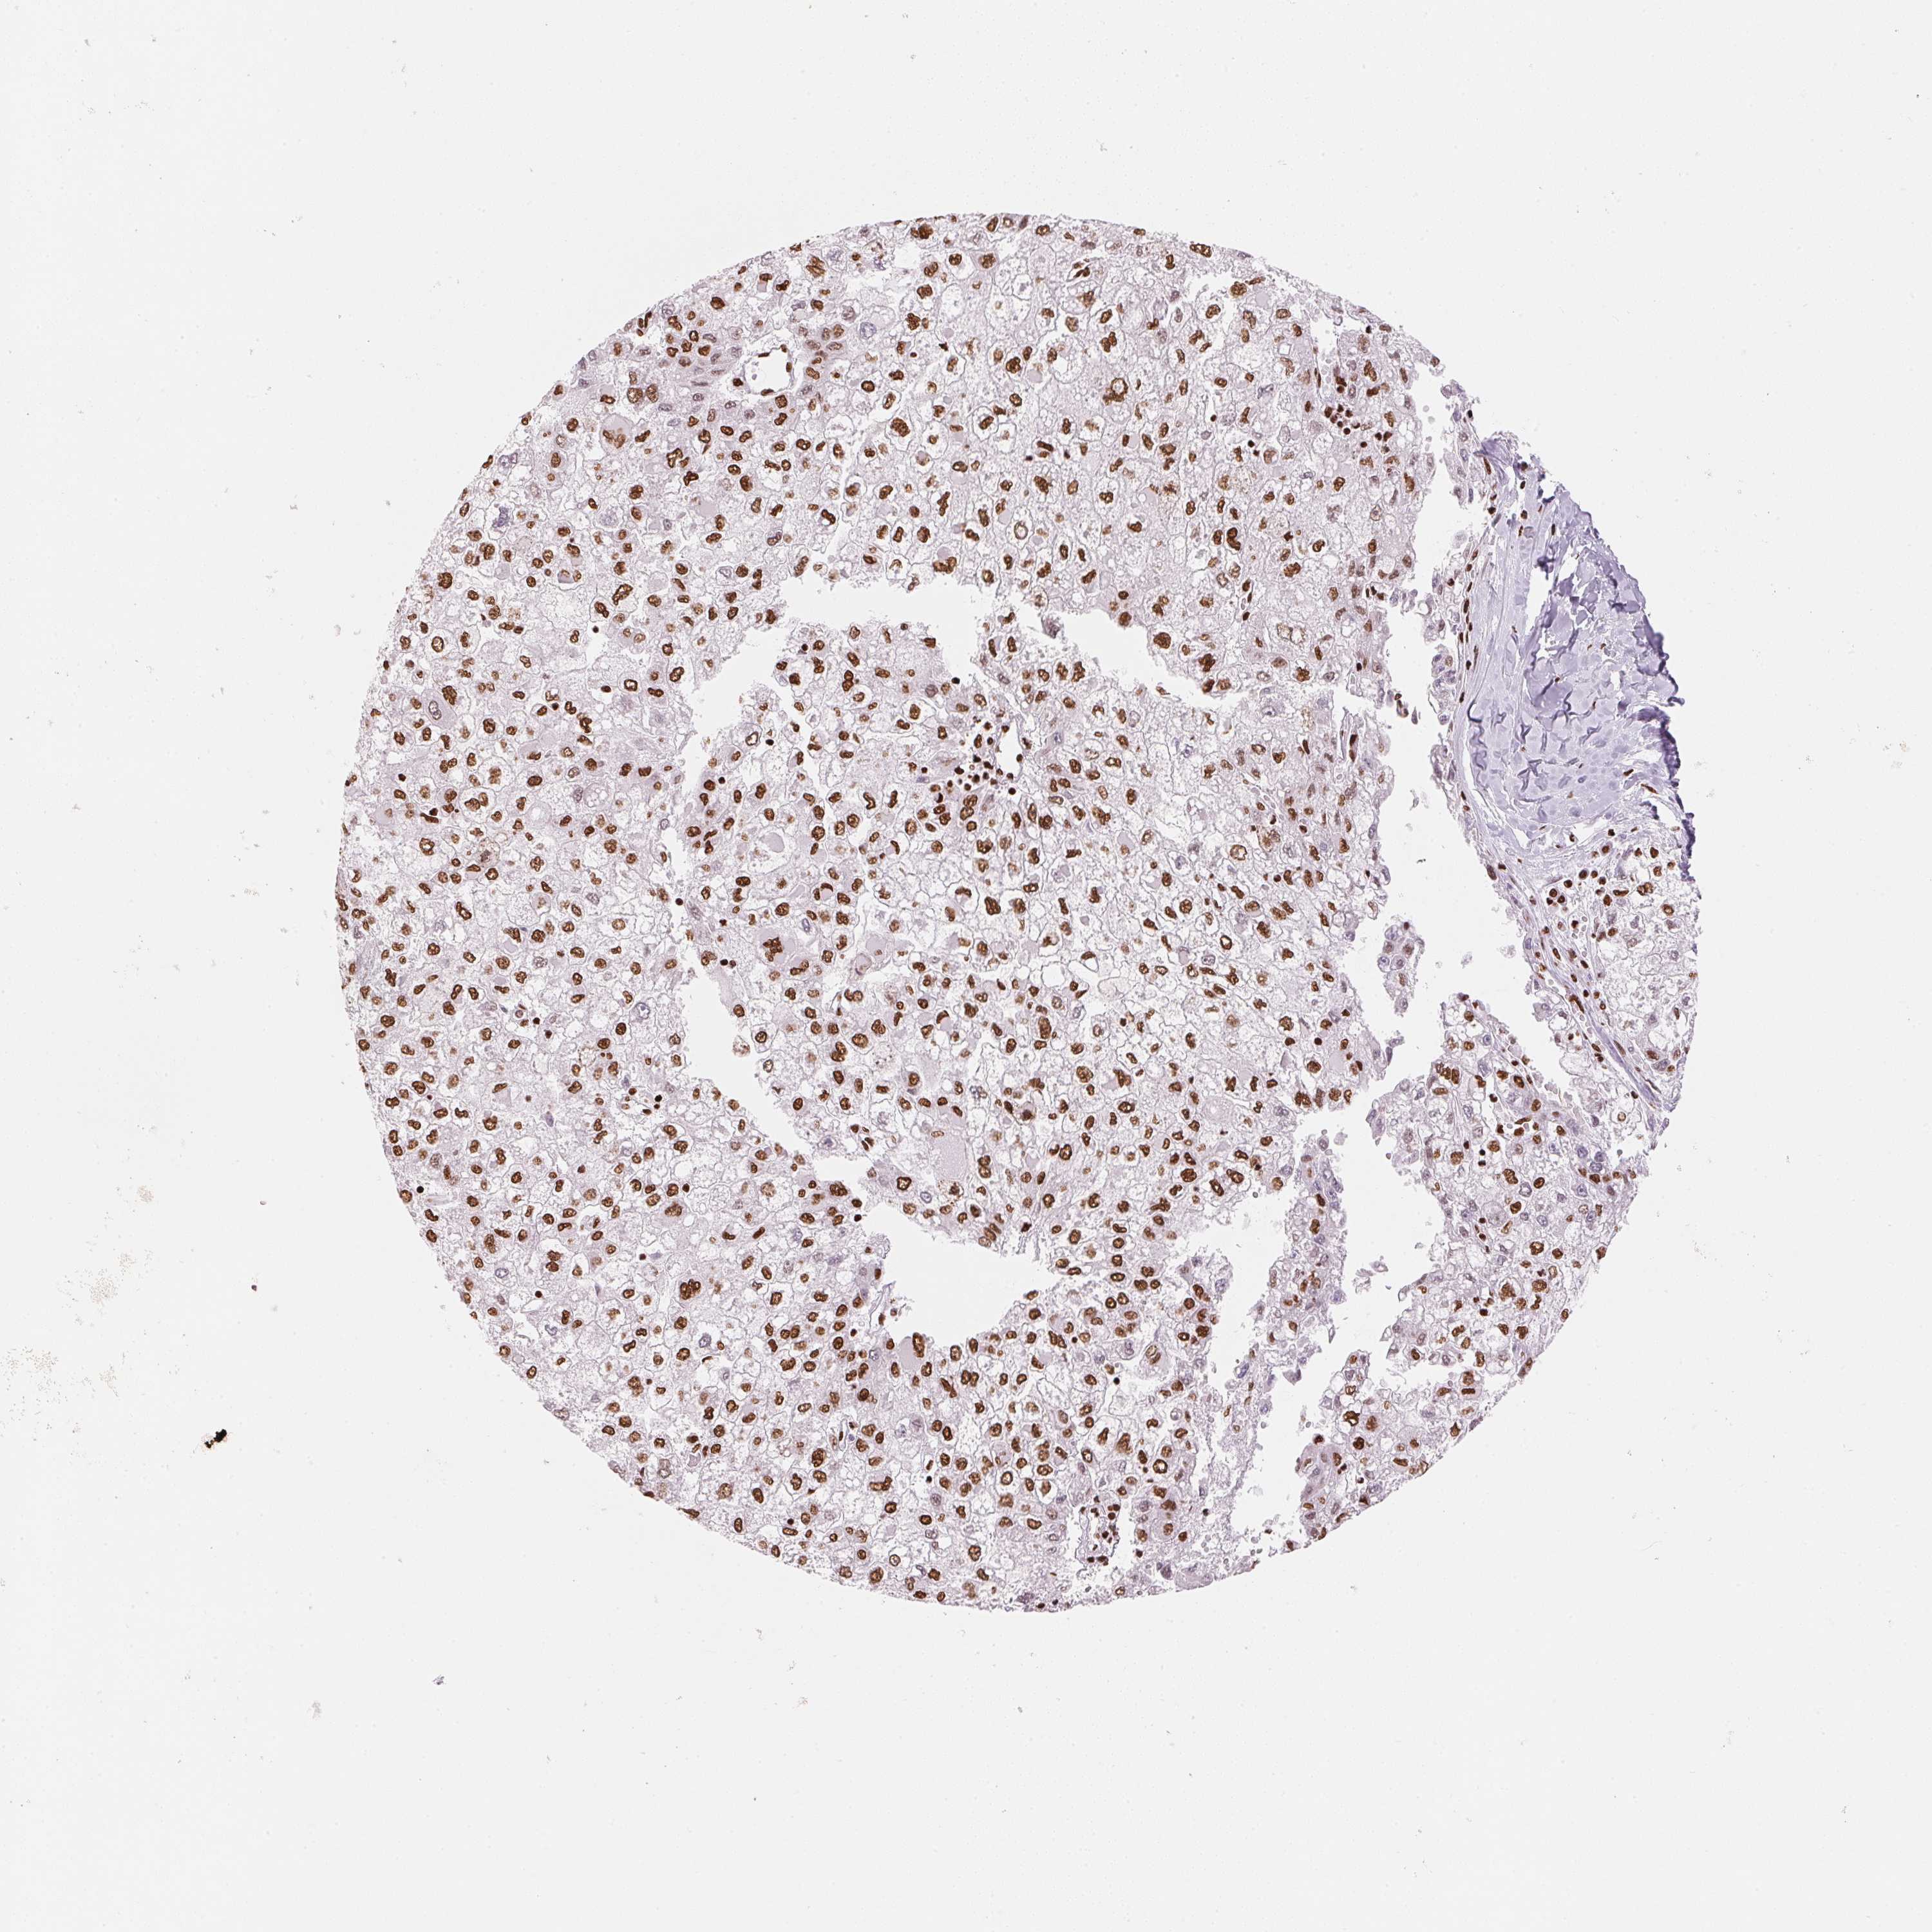

LIVER CANCER - Protein expressioni

A mouse-over function shows sample information and annotation data. Click on an image to view it in a full screen mode. Samples can be filtered based on level of antibody staining by selecting one or several of the following categories: high, medium, low and not detected. The assay and annotation is described here.

Note that samples used for immunohistochemistry by the Human Protein Atlas do not correspond to samples in the TCGA dataset.

Antibody stainingi

Antibody staining in the annotated cell types in the current human tissue is reported as not detected, low, medium, or high, based on conventional immunohistochemistry profiling in selected tissues. This score is based on the combination of the staining intensity and fraction of stained cells.

Each image is clickable and will lead to virtual microscopy that enables deeper exploration of all samples and also displays staining intensity scores, fraction scores and subcellular localization as well as patient and tissue information for each sample.

Antibody HPA061593

Antibody CAB016327

Staining

High

Medium

Low

Not detected

Intensity

Strong

Moderate

Weak

Negative

Quantity

>75%

75%-25%

<25%

None

Location

Nuclear

Cytoplasmic/membranous

Cytoplasmic/membranous,nuclear

Carcinoma, Hepatocellular, NOS

Cholangiocarcinoma